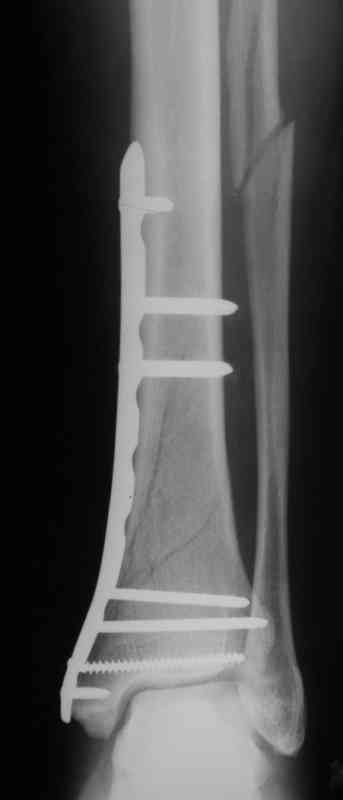

Выполнил MIPO предизогнутой метафизарной LCP

Вообщем, поздравляю!

И все же немного критики:1) Вы добивались анатомичной репозиции, которая требует абсолютной стабильности, которая в свою очередь возможноа только в условиях межфрагментарной компрессии. Пластина уложена как мостовидная, не хватает стягивающнго винта. 2) есть укорочение малоберцовой кости, необхордимо восстановить ее длину! В таком виде я бы не стал разрешать раннюю нагрузку. Добавить самую малость: стягивающий винт и остеосинтез малоберцовой кости и больной может наступать сразу.

Спасибо за критику!

В этом случае остеосинтез выполнялся малоинвазивно и я не добивался абсолютной стабильности преднамеренно. Стабильность относительная и ст. её зависит от механических свойств импланта;возможно, нужно было взять длиннее пластину, увеличив её рабочую длину

> есть укорочение малоберцовой кости, необхордимо восстановить ее длину